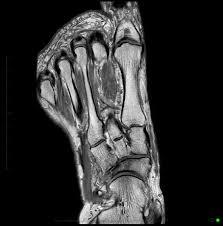

34M with forefoot pain

Psoriatic Arthritis

erosions in the metatarsophalangeal (MTP) and interphalangeal (IP) joints is nonspecific.

However, the florid periostitis strongly suggests either psoriatic arthritis or chronic reactive arthritis.